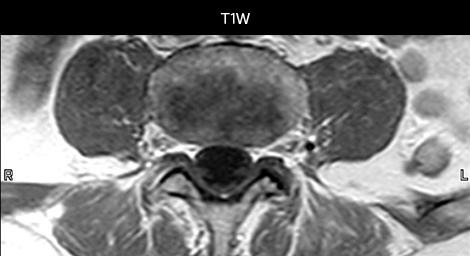

in image acquisition and postprocessing algorithms.”“mDIXON TSE sequences allow simultaneous characterization of morphological changes from the in-phase T2-weighted images and visualization of edematous changes, thanks to the water T2-weighted images from the same acquisition. Anatomical and morphological considerations could be a partial or complete ligament tear, a bony avulsion or hematoma.” “For soft tissue assessment mDIXON brings similar benefits. For example in one T2-weighted mDIXON TSE acquisition, having the multiple contrasts helps us assess abnormalities in peripheral nerves fascicles, which may be due to anatomical or inflammatory changes..” “In peripheral joints, we get good image quality in difficult areas with mDIXON TSE. Fat suppressed images appear homogeneous over the entire image, even with large coverage at 3.0T – for instance in scapular or hip girdles – or in the bearing areas or around metal prostheses*, where fat suppression is often deficient with STIR or spectral fat suppression, causing diagnostic difficulties. If a diagnostic image is right the first time, we don’t need to repeat or add a sequence.” “mDIXON TSE sequences allow simultaneous characterization of morphological changes from the in-phase T2-weighted images and visualization of edematous changes, thanks to the water T2-weighted images from the same acquisition. Anatomical and morphological considerations could be a partial or complete ligament tear, a bony avulsion or hematoma.” “For soft tissue assessment mDIXON brings similar benefits. For example in one T2-weighted mDIXON TSE acquisition, having the multiple contrasts helps us assess abnormalities in peripheral nerves fascicles, which may be due to anatomical or inflammatory changes..”

“We use mDIXON TSE extensively in our spine imaging in the emergency room,” says Dr. Karis. “It’s particularly nice in that it is very robust with regard to susceptibility type of problems that would come up with traditional spectral fat-saturated images; these problems are essentially eliminated with the mDIXON technique. In our ED environment it’s really nice to have the fat-free imaging that goes along with the mDIXON technique.